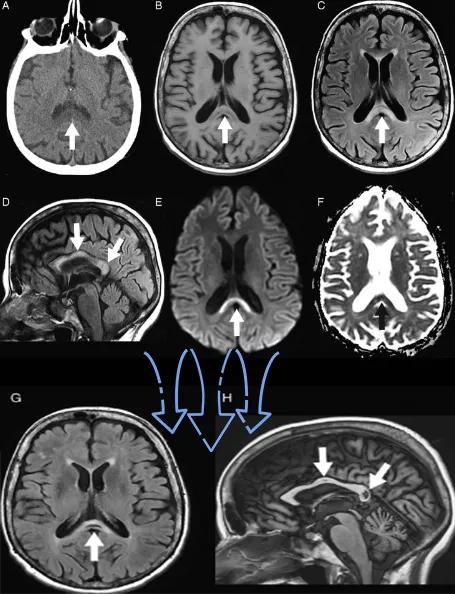

- 随着病变进展至亚急性期和慢性期,胼胝体内可出现坏死、囊变,以膝部及压部表现为著。在膝部和体部常表现为中心夹层状异常信号,类似“三明治”状,其境界清楚,据认为这是本病的特点之一。病理检查证实,病变主要对称性侵及胼胝体的中心层,而背、腹层面的组织结构相对完好。主要的组织学所见为脱髓鞘,少突胶质细胞明显减少,而含脂巨细胞大量增多。部分病例在T2加权像上,偶见胼胝体变性、坏死区内出现极低信号,镜下病理显示含脂巨细胞内可见散在或成堆的含铁血黄素分布,可能为T2异常低信号的病理基础。

上排:原发性胼胝体变性急性期

下排:原发性胼胝体变性慢性期,表现为胼胝体萎缩、软化

急性期原发性胼胝体变性(胼胝体压部及体部病变,CT呈低密度,T1WI呈稍低信号,FLAIR呈稍高信号,扩散受限)向慢性期转变,慢性期胼胝体压部病灶出现坏死或囊变,FLAIR呈低信号